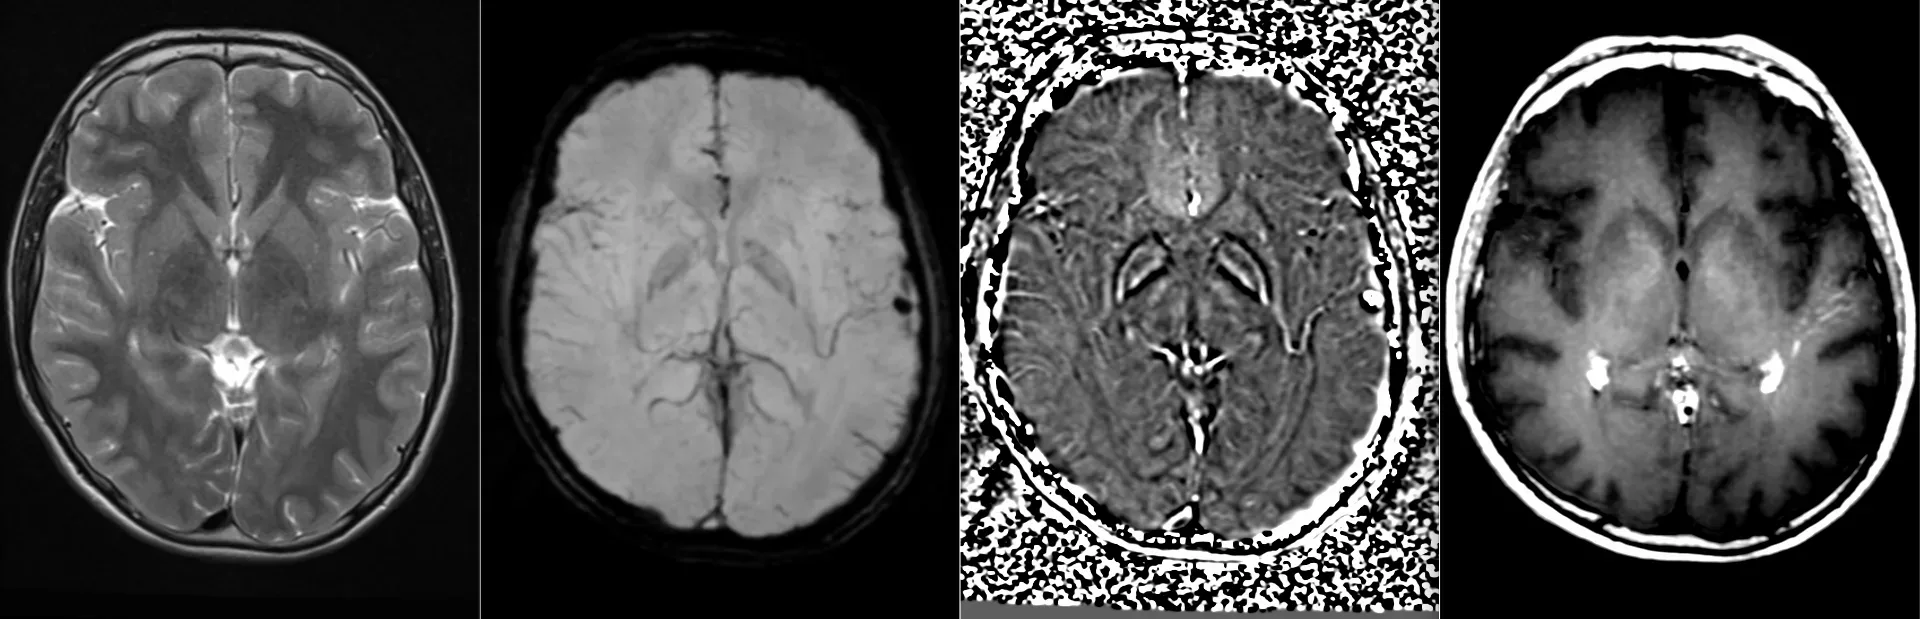

Женщина 32 года. Больной считает себя с 2024 г, когда стала отмечать онемение угла рта. Со слов пациентки ей был предварительно выставлен диагноз - РС, но дополнительных методов обследования и специфического лечения не проводилось. В настоящее время жалоб нет. В исследовании от октября 2024 отмечался очаг в левой затылочной доле с выраженным контрастированием, в настоящее время этот же очаг отмечается с сохраняющимся контрастированием. Формально - есть выполнение критериев диссеминации и в пространстве (юкстакортикальный и перивентрикулярный очаги есть), и во времени (есть усиливающиеся и неу…